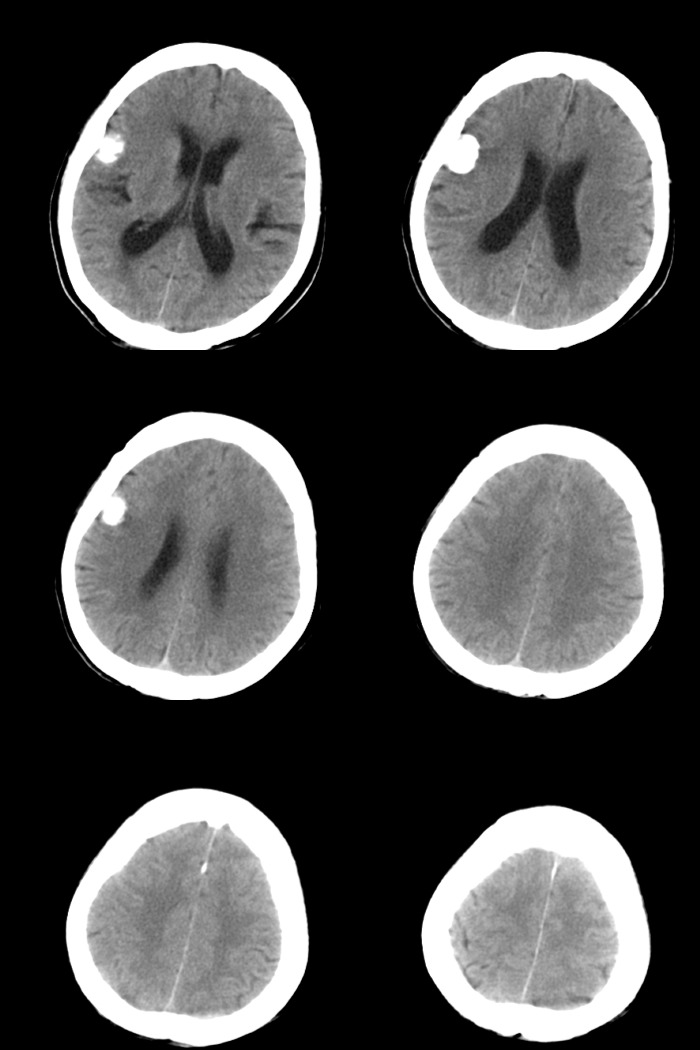

标题: CT17990:F76y,反复头昏。

76岁女性,反复头昏、头痛,余无不适。

诊断:右颞部钙化性脑膜瘤.

诊断依据:1.定位:脑外颅内--邻近脑沟增宽/脑组织受压内移/局部颅骨增生.

2.定性:良性--病灶边缘光整清楚/密度较高均匀/脑组织水肿不明显即占位效应不明显.

鉴别诊断:1.右颞骨内生骨软骨瘤/2.少突胶质细胞瘤/3.弥漫性星型细胞瘤.

1)考虑右颞部钙化性脑膜瘤。2)脑萎缩。

考虑脑膜瘤可能性大,如果是骨软骨瘤应该是广基底与颞骨相连,本例没有发现;当然应该在病灶范围内行薄层扫描进一步查明其与颞骨的关系对诊断有帮助。